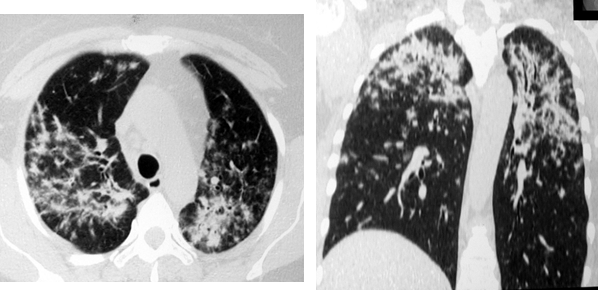

Картина фиброзных изменений при саркоидозе может достигать различной степени выраженности (от минимальной до грубой деформации легочного рисунка) и формируется постепенно. При хронически текущем саркоидозе, в случаях его позднего выявления, фиброз нередко оказывается первым признаком по данным лучевой визуализации и симулирует силикоз или туберкулёз. При формировании фиброза при саркоидозе часто происходит смещение главных бронхов, образование буллезных «сот», главным образом на периферии, и диффузное распространение линейных теней в легочной ткани (рис. 6).

Рис. 6. РК-томограммы больной Ч., 53 лет. Распространённый пневмофиброз с элементами буллёзной эмфиземы

Довольно часто при саркоидозе в процесс вовлекается плевра, в виде её утолщения от нерезко выраженного до массивного, иногда с элементами обызвествления (рис. 7).

Рис. 7. РК-томограммы пациентки Ф., 59 лет. Определяются участки уплотнения лёгочной ткани субплевральной локализации с вовлечением в процесс костальной и междолевой плевры